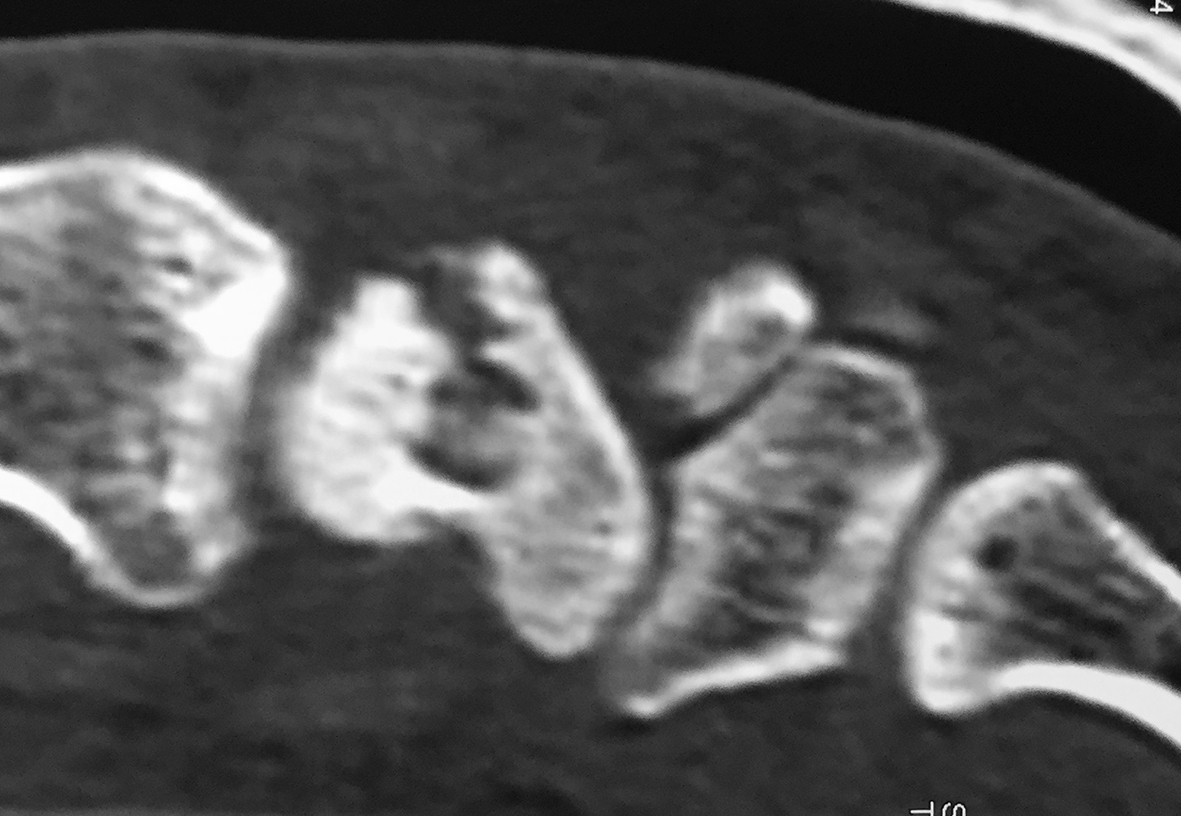

Figura 3: Caso 9

a) Radiografia de perfil pre-opertaoria

b) TC pre-operatoria. Corte sagital

c) TC pre-operatoria. Corte coronal

d) Radiografías post-operatorias

e) Radiografía de frente, 33 meses seguimiento, pseuodartrosis persistente

f) Radiografía de frente, 33 meses seguimiento, pseuodartrosis persistente